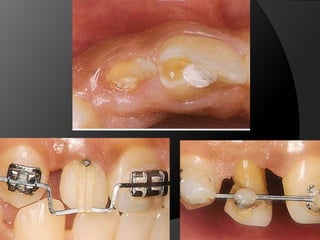

fundamentos de periodoncia en prótesis fijaCuando, por la evolución de lesiones de caries, fracturas, o necesidad de ganancia de retención mecánica en pilares muy cortos, el espacio biológico es violado, existe la necesidad de restablecer sus dimensiones, como una forma de recuperar la salud del periodonto y de facilitar los procedimientos protésicos

fundamentos de periodoncia en prótesis fijaCirugía de Alargamiento CoronalExtrusión OrtodónticaTécnica Combinada

fundamentos de periodonciaen prótesis fijaCuando, por la evolución de lesiones de caries, fracturas, o necesidad de ganancia de retención mecánica en pilares muy cortos, el espacio biológico es violado, existe la necesidad de restablecer sus dimensiones, como una forma de recuperar la salud del periodonto y de facilitar los procedimientos protésicos

fundamentos de periodonciaen prótesis fijaCirugía de Alargamiento CoronalExtrusión OrtodónticaTécnica Combinada